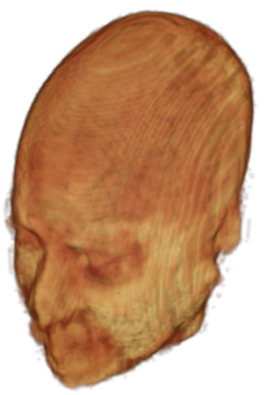

The digitalization of heath records has increased the risk of –and impact of– large scale data leaks. Although data compliance standards have been enacted to protect health records (HIPAA and GDPR), privacy of medical data is a growing concern. Three-dimensional scans such as magnetic resonance images (MRI) and computed tomography (CT), for example, contain an intrinsic privacy risk [Lotan et al.(2020)Lotan, Tschider, Sodickson, Caplan, Bruno, Zhang, and Lui]. Detailed renderings of the head can be crafted from 3D scans using techniques such as volumetric raycasting, as in Figure 1. This vulnerability can expose the patient’s identity if the renderings are matched to a face database [Mazura et al.(2012)Mazura, Juluru, Chen, Morgan, John, and Siegel, Lotan et al.(2020)Lotan, Tschider, Sodickson, Caplan, Bruno, Zhang, and Lui].

To prevent these types of attack, medical scans are currently de-identified using crude removal-based techniques [Bischoff-Grethe et al.(2007)Bischoff-Grethe, Ozyurt, Busa, Quinn, Fennema-Notestine, Clark, Morris, Bondi, Jernigan, Dale, Brown, and Fischl, Schimke et al.(2011)Schimke, Kuehler, and Hale, Milchenko and Marcus(2013)] which seek to remove privacy-sensitive parts of the head (examples in Figure 3). However, as we demonstrate, these existing techniques fail to reliably hide the patient’s identity – or they are so aggressive that they impair further medical analyses. A better solution is needed.

Benchmark De-Identification Methods. We compare our result with three publicly available and widely-established methods for de-identification of MRI head scans, depicted in Figure 3. All methods have in common that they (1) are not deep-learning-driven, (2) require no additional training and (3), are used on a day-to-day basis in neuroscience and clinical research. All procedures were applied with default settings on images of resolution . The methods include QUICKSHEAR [Schimke et al.(2011)Schimke, Kuehler, and Hale], FACE MASK [Milchenko and Marcus(2013)], and DEFACE [Bischoff-Grethe et al.(2007)Bischoff-Grethe, Ozyurt, Busa, Quinn, Fennema-Notestine, Clark, Morris, Bondi, Jernigan, Dale, Brown, and Fischl]. Descriptions of the methods are provided in the Appendix. We also include MRI WATERSHED [Ségonne et al.(2004)Ségonne, Dale, Busa, Glessner, Salat, Hahn, and Fischl], a skull-stripping method that removes everything except the brain.